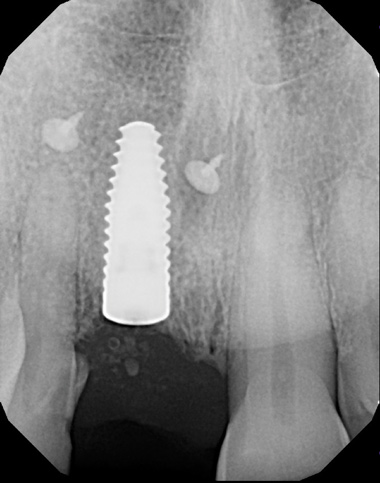

(6.) Pretreatment periapical radiograph.

Figure 6